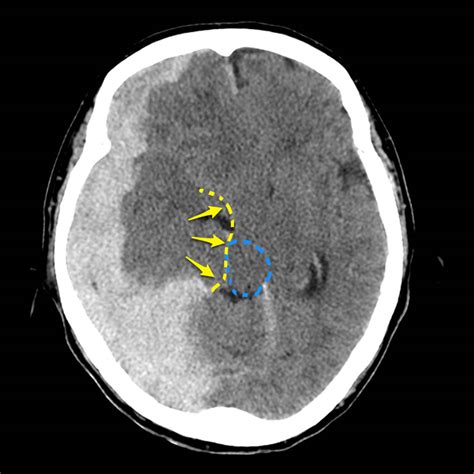

• Imaging Studies: Imaging techniques such as CT scans and MRI are crucial for visualizing the brain and detecting any shifts or abnormalities. These tests can provide detailed images of the brain’s structure and help identify the cause of the midline shift.